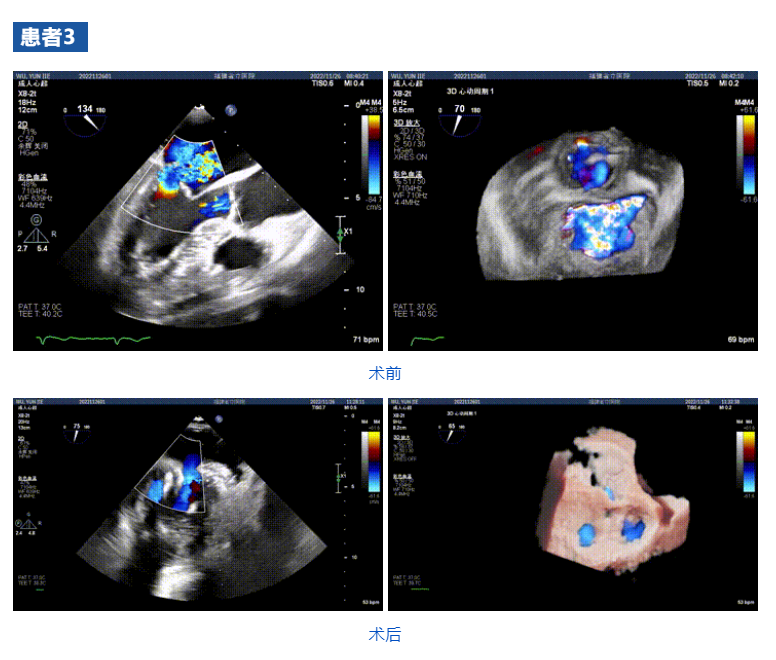

接受治療的三例患者均為器質(zhì)性重度二尖瓣反流(DMR)患者,術(shù)前超聲提示二尖瓣后葉脫垂伴4+反流,左室舒張功能減退。郭延松教授攜同團(tuán)隊成員陳新敬副教授和洪景宣、方明程、楊清勇主治醫(yī)師、心外科丁杭主任以及超聲科賴寶春、葉振盛主治醫(yī)師共同進(jìn)行病情討論??紤]到患者高齡、基礎(chǔ)疾病多、STS評分高,為外科手術(shù)極高?;颊?,不適合進(jìn)行外科開胸二尖瓣手術(shù),因此決定為患者實施經(jīng)導(dǎo)管緣對緣修復(fù)介入術(shù)(JensClip經(jīng)導(dǎo)管瓣膜夾系統(tǒng))。

在浙江大學(xué)醫(yī)學(xué)院附屬第二醫(yī)院王建安教授團(tuán)隊的支持下,手術(shù)經(jīng)股靜脈-房間隔入路,采用全身麻醉插管,在TEE和DSA引導(dǎo)下完成房間隔穿刺。置入JensClip瓣膜夾系統(tǒng)后,在左房調(diào)整瓣膜夾的位置和軸向,后進(jìn)入左室,在TEE引導(dǎo)下捕捉二尖瓣前后瓣葉,并關(guān)閉瓣膜夾。經(jīng)TEE反復(fù)確認(rèn)手術(shù)效果后最終鎖定并釋放瓣膜夾。術(shù)后即刻超聲顯示瓣膜夾位置穩(wěn)定,功能良好,二尖瓣反流由術(shù)前4+減少至微量,手術(shù)圓滿成功。